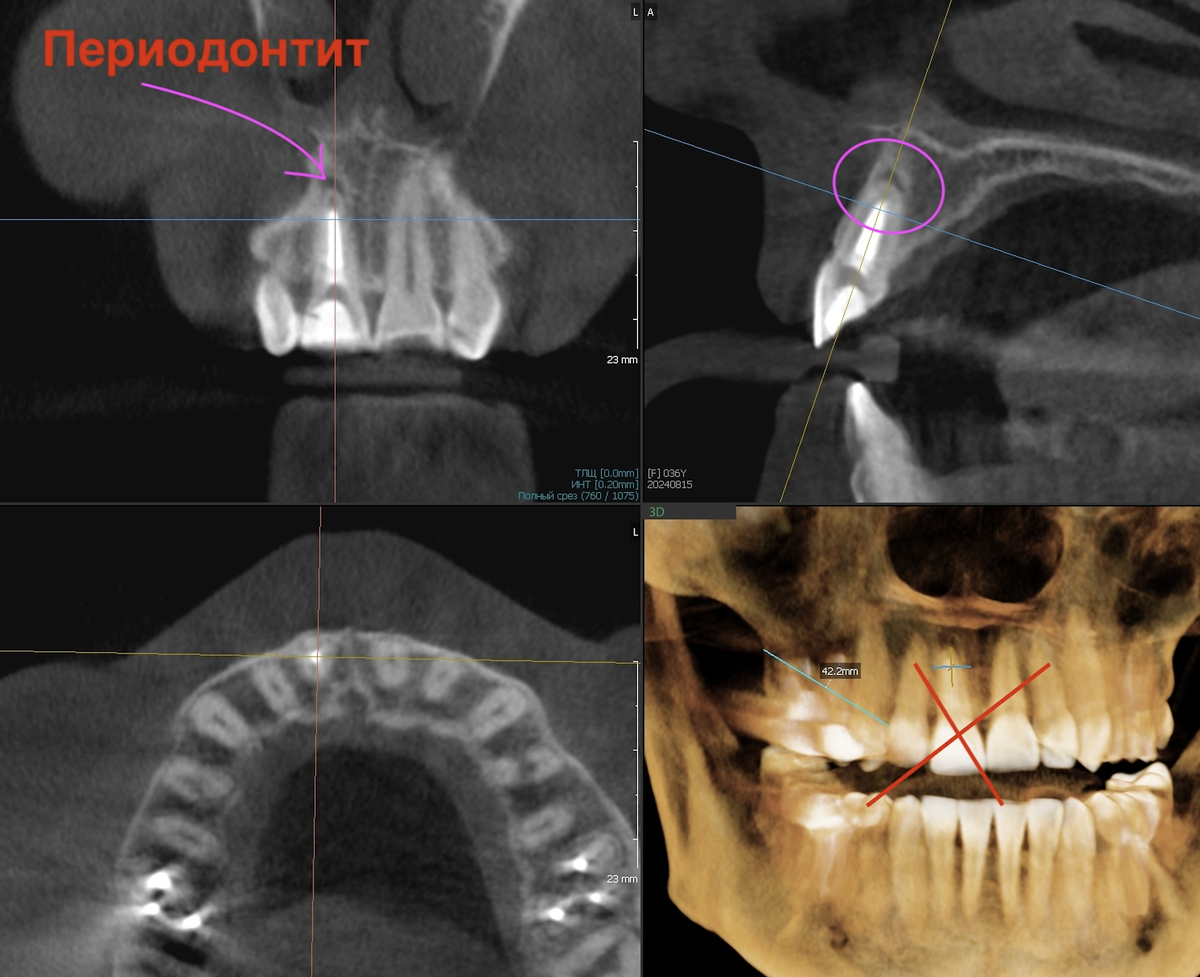

Зуб на кого то